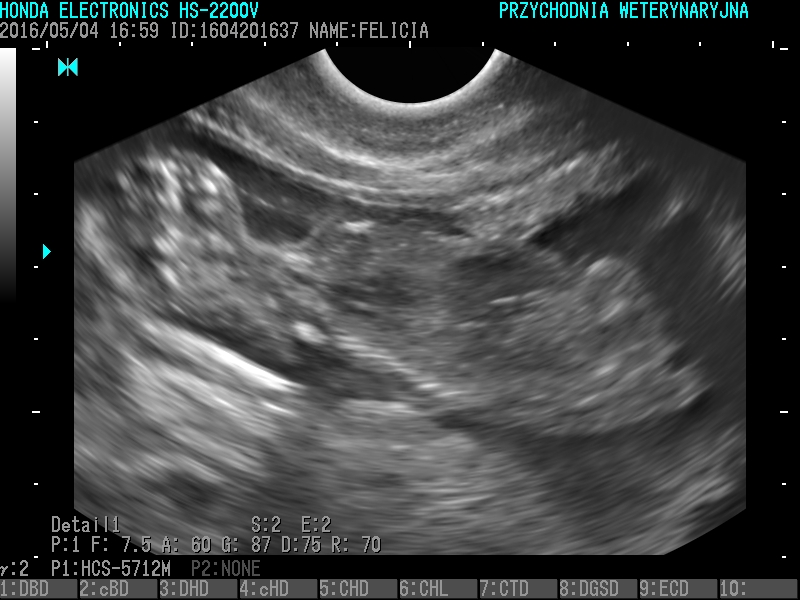

USG

- wykrywanie ciąży, ropomacicza, kamicy moczowej, guzów narządów, wodobrzusza, chorób prostaty, chorób pęcherza moczowego, chorób serca

Badanie USG pozwala na ocenę struktury narządów. Zaletą jest nieinwazyjność, może być wykonywane choćby codziennie. Ważne jest odpowiednie przygotowanie pacjenta do badania- kilkunastogodzinna głodówka i nie oddawanie moczu przez przynajmniej 2 godziny przez badaniem.